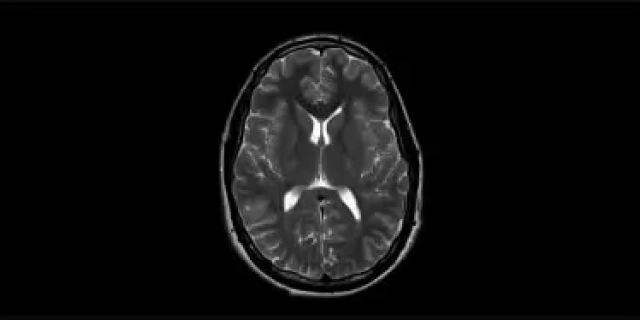

Magnetische Resonantie Basis

Opleiding tot zelfstandig functionerend radiodiagnostisch laborant, met specialisatie magnetische resonantie.